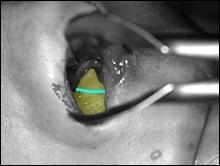

A téma ez a fejezet - acanthion. Acanthion - ez terjed ki előre a csontképződést, található az alapja az orr. A jobb felső fotó rajta a sárga nyíl.

Mielőtt nagyobb acanthion. Ez az, amit úgy néz ki, a művelet során. Az ábrán a jobb ez sárga színű. Acanthion columella található, közvetlenül alatta, ahol a felső ajak határos az alapja az orrát.

Része a gerinc, amelyeket el kell távolítani jelzi a kék vonalon. Removal végezzük vésővel.

A fotó távoli nazális gerinc. On line távolság centiméterben, és a fekete nyíl képviseli a távolság egy inch.

A jobb felső sarokban a kép jól látható acanthion (sárga színnel jelöltek). Az alsó képen az azonos, de a távoli nazális gerinc.

A hossza a kék nyíl egyenlő egy hüvelyk.

A felső és az alsó képen látható két legkiemelkedőbb nazális gerinc, a jobb kilátás bővítették segítségével horgokat.